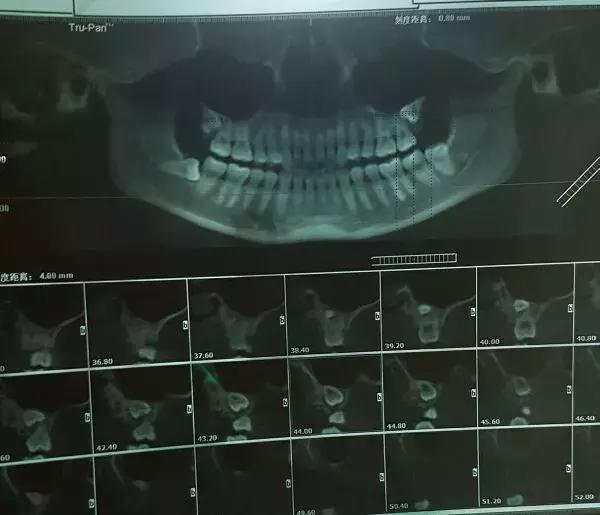

附上几个带牙片诊断

1、长成这样的智齿需要拔吗?

你的左下智齿是完全埋伏的阻生齿,在确定没有实质的危害的情况下可以不拔。什么叫实质的危害呢?比如,是不是顶到了前牙,引起了左下7的牙根吸收?比如,有没有产生了含牙囊肿?比如有没有产生了你无法忍受的症状——主观或客观?怎么看?拍 CBCT 看。一张曲面断层片看到的信息是不够的。如果 CBCT 显示没有左下 7 牙根吸收、没有含牙囊肿等等,就先留着吧。

5、这种情况咋回事?要拔吗?

智齿下面的牙齿是下颌双尖牙异位了,位置很深,需要定期密切观察。和智齿一起拔的话,骨折风险不低。即便拔,建议拍个CBCT,住院拔。